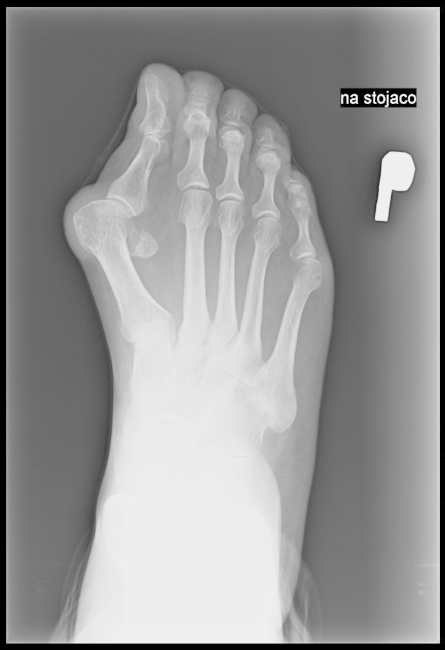

Na zamieszczonej ilustracji przedstawiono ułożenie pacjenta do wykonania zdjęcia rentgenowskiego

A. palców stopy.

B. stopy.

C. śródstopia.

D. kości piętowej.